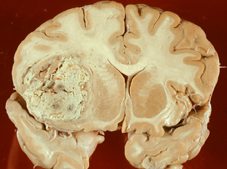

- Laut GNM gibt es keine Hirntumoren. Diese widersprächen ihren biologischen Gesetzen, da das Zielorgan gleichzeitig Ort der Konfliktentstehung nach Hamer wäre. Daher werden sie einfach wegdefiniert. Rita Levy-Montalcini erhielt den Nobelpreis für die Entdeckung der Teilungsfähigkeit von Nervenzellen. Ein Vielzahl von unterschiedlichen Hirntumoren sind exakt beschrieben und lassen sich unterscheiden: Astrozytome, Glioblastome, Ependymome, Pinealome, Schwannome, Menigeome und so weiter und so fort.